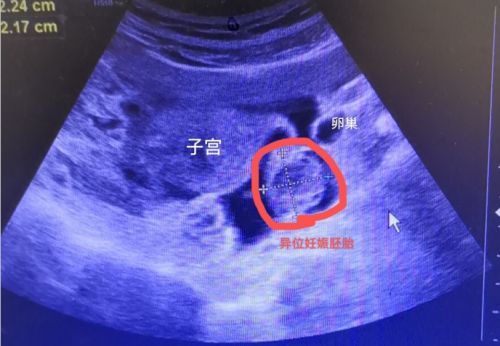

B超发现,子宫与卵巢之间有一个包块。

7月20日上午,22岁的小雨忽然下腹部剧烈疼痛、头晕、乏力、面色苍白,由母亲搀扶紧急送至捷克论坛 天心阁院区。妇科黄薇主任接诊后,立即为她做了尿妊娠检查,结果为阳性;腹部+妇科B超提示:子宫与卵巢之间有一个鸡蛋大小的包块;盆腹腔有大量积液;阴道后穹隆穿刺抽出8ml暗红色不凝血,考虑为“异位妊娠破裂出血,失血性休克”。